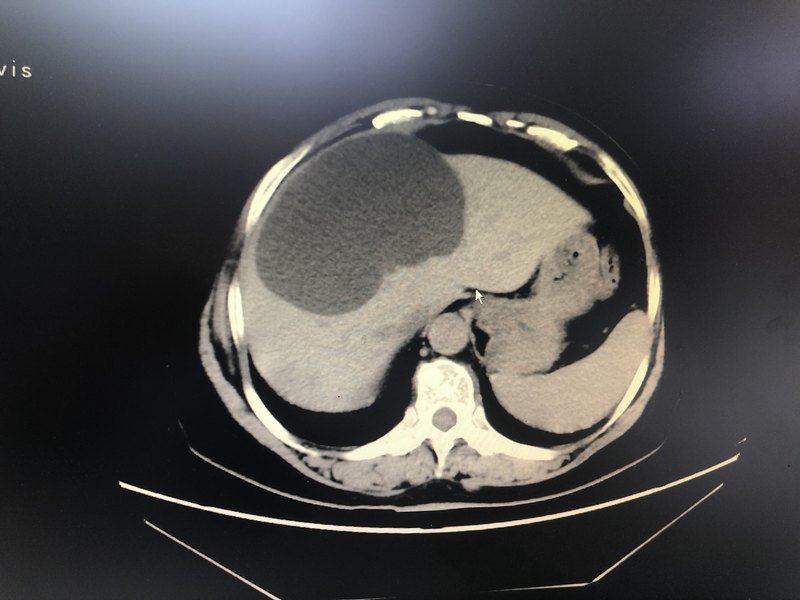

患者體檢發(fā)現(xiàn)肝囊腫,巨大體型,CT提示肝多發(fā)囊腫,右葉巨大。給予腹腔鏡下肝囊腫開窗引流,手術順利,術后恢復良好。病理為肝囊腫及急慢性炎?,F(xiàn)在患者活動自如。生活良好。